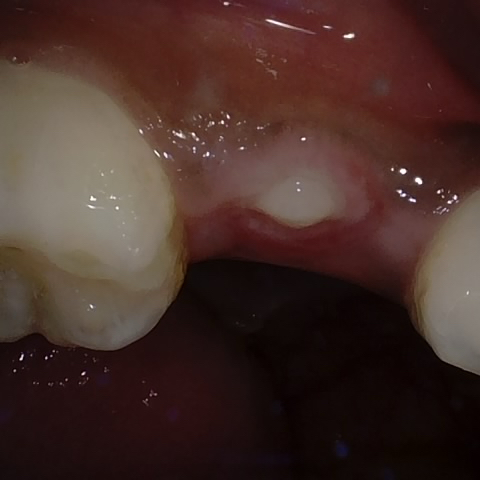

Annotated as "Good"